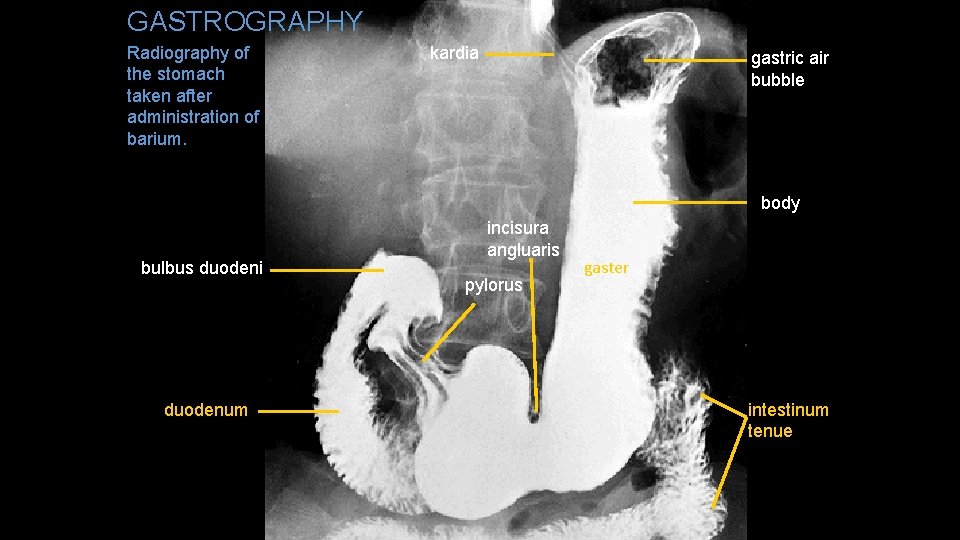

GASTROGRAPHY Radiography of the stomach taken after administration of barium. kardia gastric air bubble body bulbus duodeni duodenum incisura angluaris pylorus gaster intestinum tenue